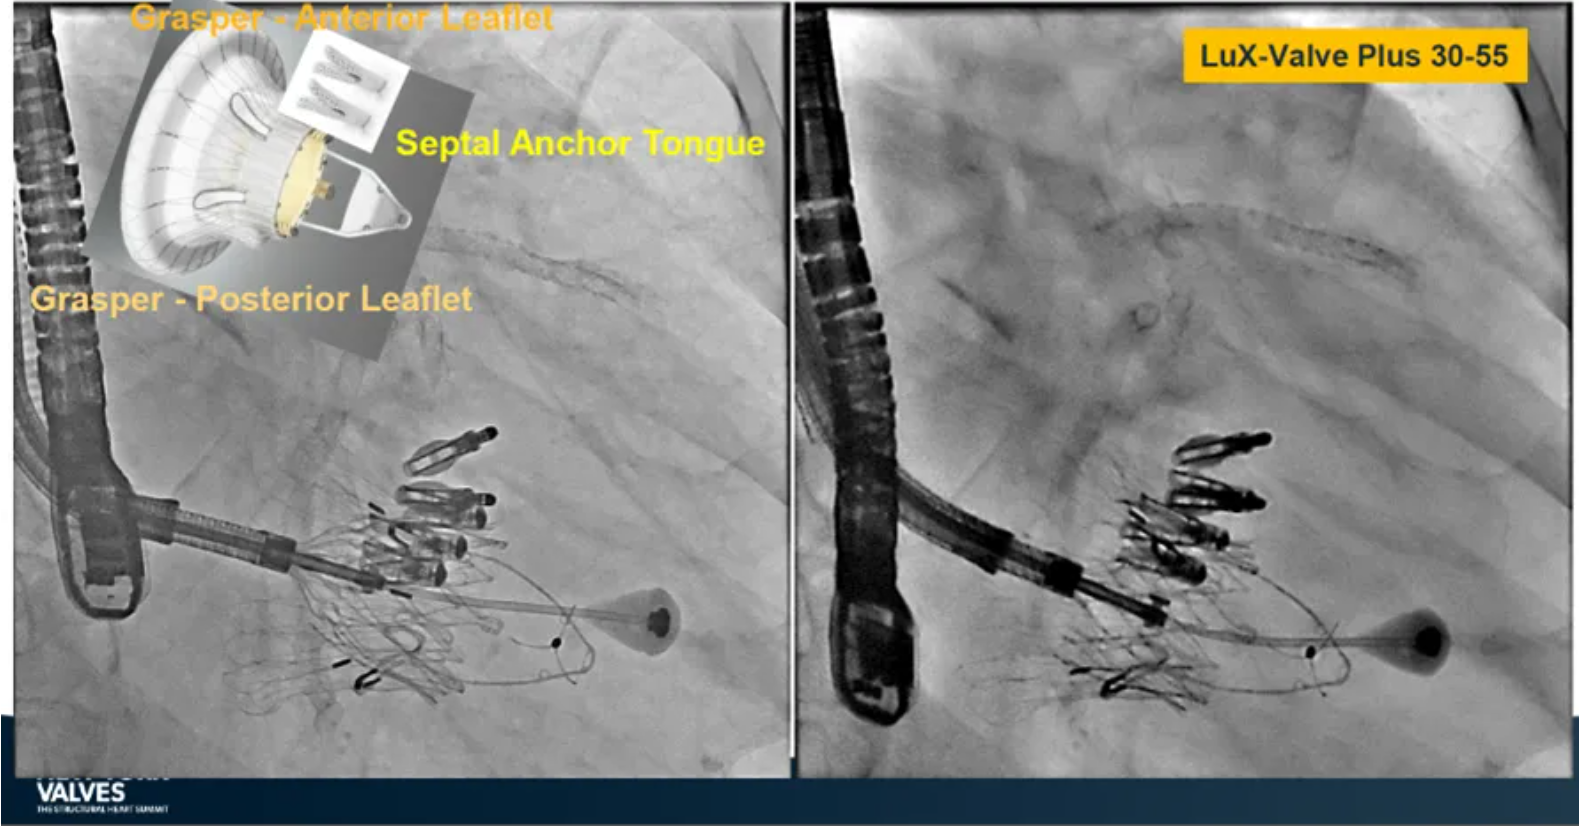

Granada教授表示,LuX-Valve Plus是一款不依賴于徑向支撐力固定的多功能TTVR器械,它的創(chuàng)新設(shè)計(室間隔錨定和瓣葉夾持件)提供了多樣的固定和穩(wěn)定技術(shù)。多中心臨床試驗研究TRAVEL II 展現(xiàn)了LuX-Valve Plus的安全性和有效性,能實現(xiàn)較短的器械操作時間,較低的復(fù)合事件發(fā)生率,并在6個月期時顯著降低三尖瓣反流等級,以及帶來心功能和生活質(zhì)量等指標(biāo)上的明顯改善。

蘇澤宇教授介紹到,受限于三尖瓣特殊的解剖結(jié)構(gòu)及后期病理性改變,并非所有的解剖都適用于T-TEER療法及外科手術(shù)進(jìn)行治療,因此TTVR器械的選擇成為了新的臨床需求,并帶來完全消除反流等級的可能性。LuX-Valve Plus即是這樣一款經(jīng)頸靜脈入路的三尖瓣置換系統(tǒng),能覆蓋較廣范圍的瓣環(huán)尺寸,并帶來較低的起搏器植入率。

來自中國上海復(fù)旦大學(xué)附屬中山醫(yī)院的魏來教授在2024年臺北瓣膜高峰論壇上分享了他使用LuX-Valve Plus治療三尖瓣反流的經(jīng)驗。魏來教授闡述道,隨著療法演變,目前全球市場有以LuX-Valve Plus及其他產(chǎn)品為代表的經(jīng)導(dǎo)管三尖瓣介入置換系統(tǒng),逐漸成為重度三尖瓣反流的一線治療方案。他介紹到,LuX-Valve Plus創(chuàng)新的室間隔錨定和經(jīng)頸靜脈入路的方式,能夠帶來安全穩(wěn)定的錨定效果及較短的輸送行程;其可調(diào)彎的輸送系統(tǒng)能保證同軸性,從而快速和安全地將人工瓣膜送達(dá)目標(biāo)手術(shù)區(qū)域,有效降低入路周邊解剖組織并發(fā)癥及術(shù)中出血風(fēng)險。